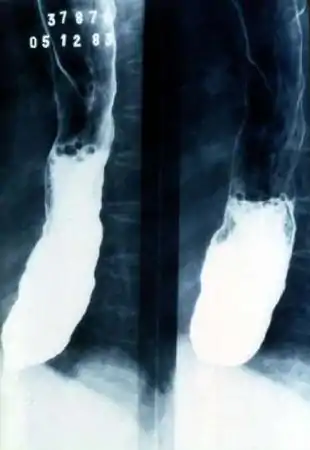

![]() Megaesófago en Enfermedad de Chagas | ||

El megaesófago puede aparecer como consecuencia de enfermedades como la acalasia o la enfermedad de Chagas. La acalasia es causada por una pérdida de células ganglionares en el plexo mientérico. Existe una marcada falta de contracción dentro de los músculos involucrados en la peristalsis con una contracción constante del esfínter esofágico inferior. La dilatación del esófago resulta en una dificultad para tragar. También se observa la retención del bolo alimenticio .